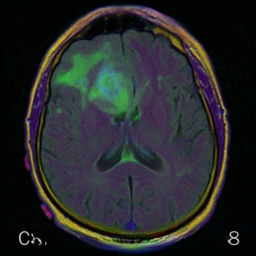

2、Brats2018多模态脑部数据集

Brats 数据集(Brain Tumor Segmentation Benchmark)是专门用于脑肿瘤分割任务的重要医学影像基准数据集。该数据集由来自多个不同医疗机构提供的多模态 MRI 扫描图像构成,并旨在促进脑肿瘤分割算法的研究与性能评估。该集合涵盖了四种不同的 MRI 模式:T1、T2、T1cecho 以及 Flair 成像技术下的高质量参考标注

数据处理方式为:采用分层切片法将3D图像数据经过分层切片处理得到二维图片,并接着使用分割标签来创建检测框。

经过良好处理后的VOC格式的数据集中,在图像中的单个模态中总计共有15,424张图像,其中类型标签主要集中在病灶区域,并且包含来自四个不同模态的VOC数据